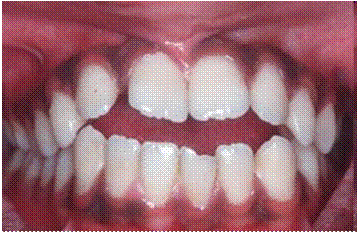

При осмотре полости рта определяется вертикальная щель между зубами во фронтальном участке при смыкании зубных рядов, отсутствие контактов в области резцов и нижних клыков (рис. 3.2.2).

Рис. 3.2.2. Фото больного «Г», 23 года, контрольная группа. Определяется вертикальная щель между зубами во фронтальном участке при смыкании зубных рядов, отсутствие контактов в области резцов и нижних клыков.